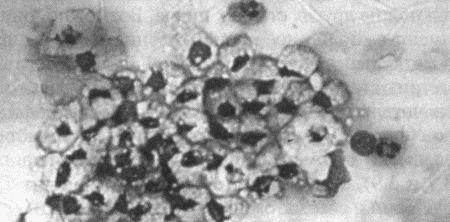

Вагинальная цитология

Повышение концентрации эстрадиола в период проэструса стимулирует деление клеток в базальных слоях вагинального эпителия, но затем концентрация эстрадиола, а соответственно и эндокринная поддержка образования нового, многослойного эпителия снижается, поэтому в образце обнаруживается больше мертвых ороговевших клеток. По мере развития проэструса снижается количество эпителиальных клеток, содержащих ядро. С начала до середины проэструса в вагинальных мазках обнаруживают повышенное содержание эритроцитов. Пик ороговения совпадает с началом повышения концентрации прогестерона; однако в начале эструса исследование не обнаруживает характерных особенностей, которые могли бы указывать на начало фертильного периода. Как правило, такой период наступает несколькими днями позже (табл. 1.1). Тем не менее вагинальная цитология остается популярным методом определения репродуктивного статуса суки из-за своей дешевизны, простоты и доступности. Для получения образца используют ватный тампон, предпочтительно небольшой, который вводят во влагалище и осторожно берут мазок. Полученные клетки помещают под микроскоп, а затем окрашивают контрастным (трихромом) или неконтрастным (например, препаратом Diff-Quik) веществом. При таком окрашивании мертвые кератинизированные клетки становятся оранжевыми, тогда как активные ядерные клетки, а также базальные и парабазальные эпителиальные клетки приобретают различные оттенки от голубого до зеленого.

Ближе к окончанию эструса вагинальные выделения претерпевают характерные изменения (снова выявляются эпителиальные клетки, содержащие ядро, и появляется большое количество лейкоцитов). Такая картина обычно наблюдается через 7–9 дней после пика ЛГ и известна как «вагинальный мазок метэструса». Изменению характера выделений предшествует переходный период, характеризующийся возрастающим количеством активных клеток и указывающий на окончание фертильного периода и эструса (табл. 1.1).

Вагинальная цитология весьма информативна в плане определения фазы эстрального цикла, однако значительные расхождения во времени появления основных признаков эструса по отношению к пику фертильности ограничивает применение указанной методики.

Фиг. 2.2.

Вагинальные выделения кошки (а). Выделения, типичные для фазы эструса. Большая часть клеток представляет собой безъядерные кератинизированные клетки или клетки с пикнотическим ядром. Присутствуют промежуточные клетки (b). Выделения, характерные для метэструса, — «течки», иногда наблюдаемой у кошек в конце эструса. Присутствуют поверхностные и промежуточные клетки, повышено содержание лейкоцитов. Этот короткий метэструс наблюдается в течение 24–48 часов (см. Приложение)